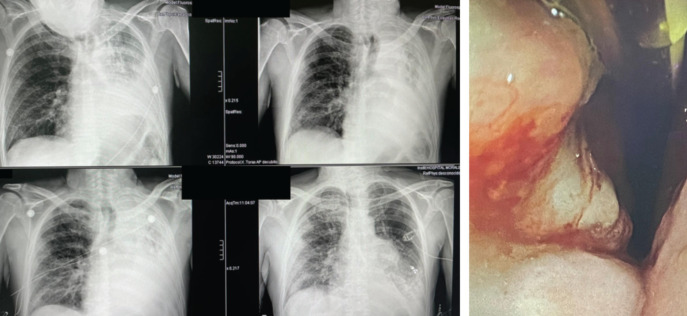

Abstract Image